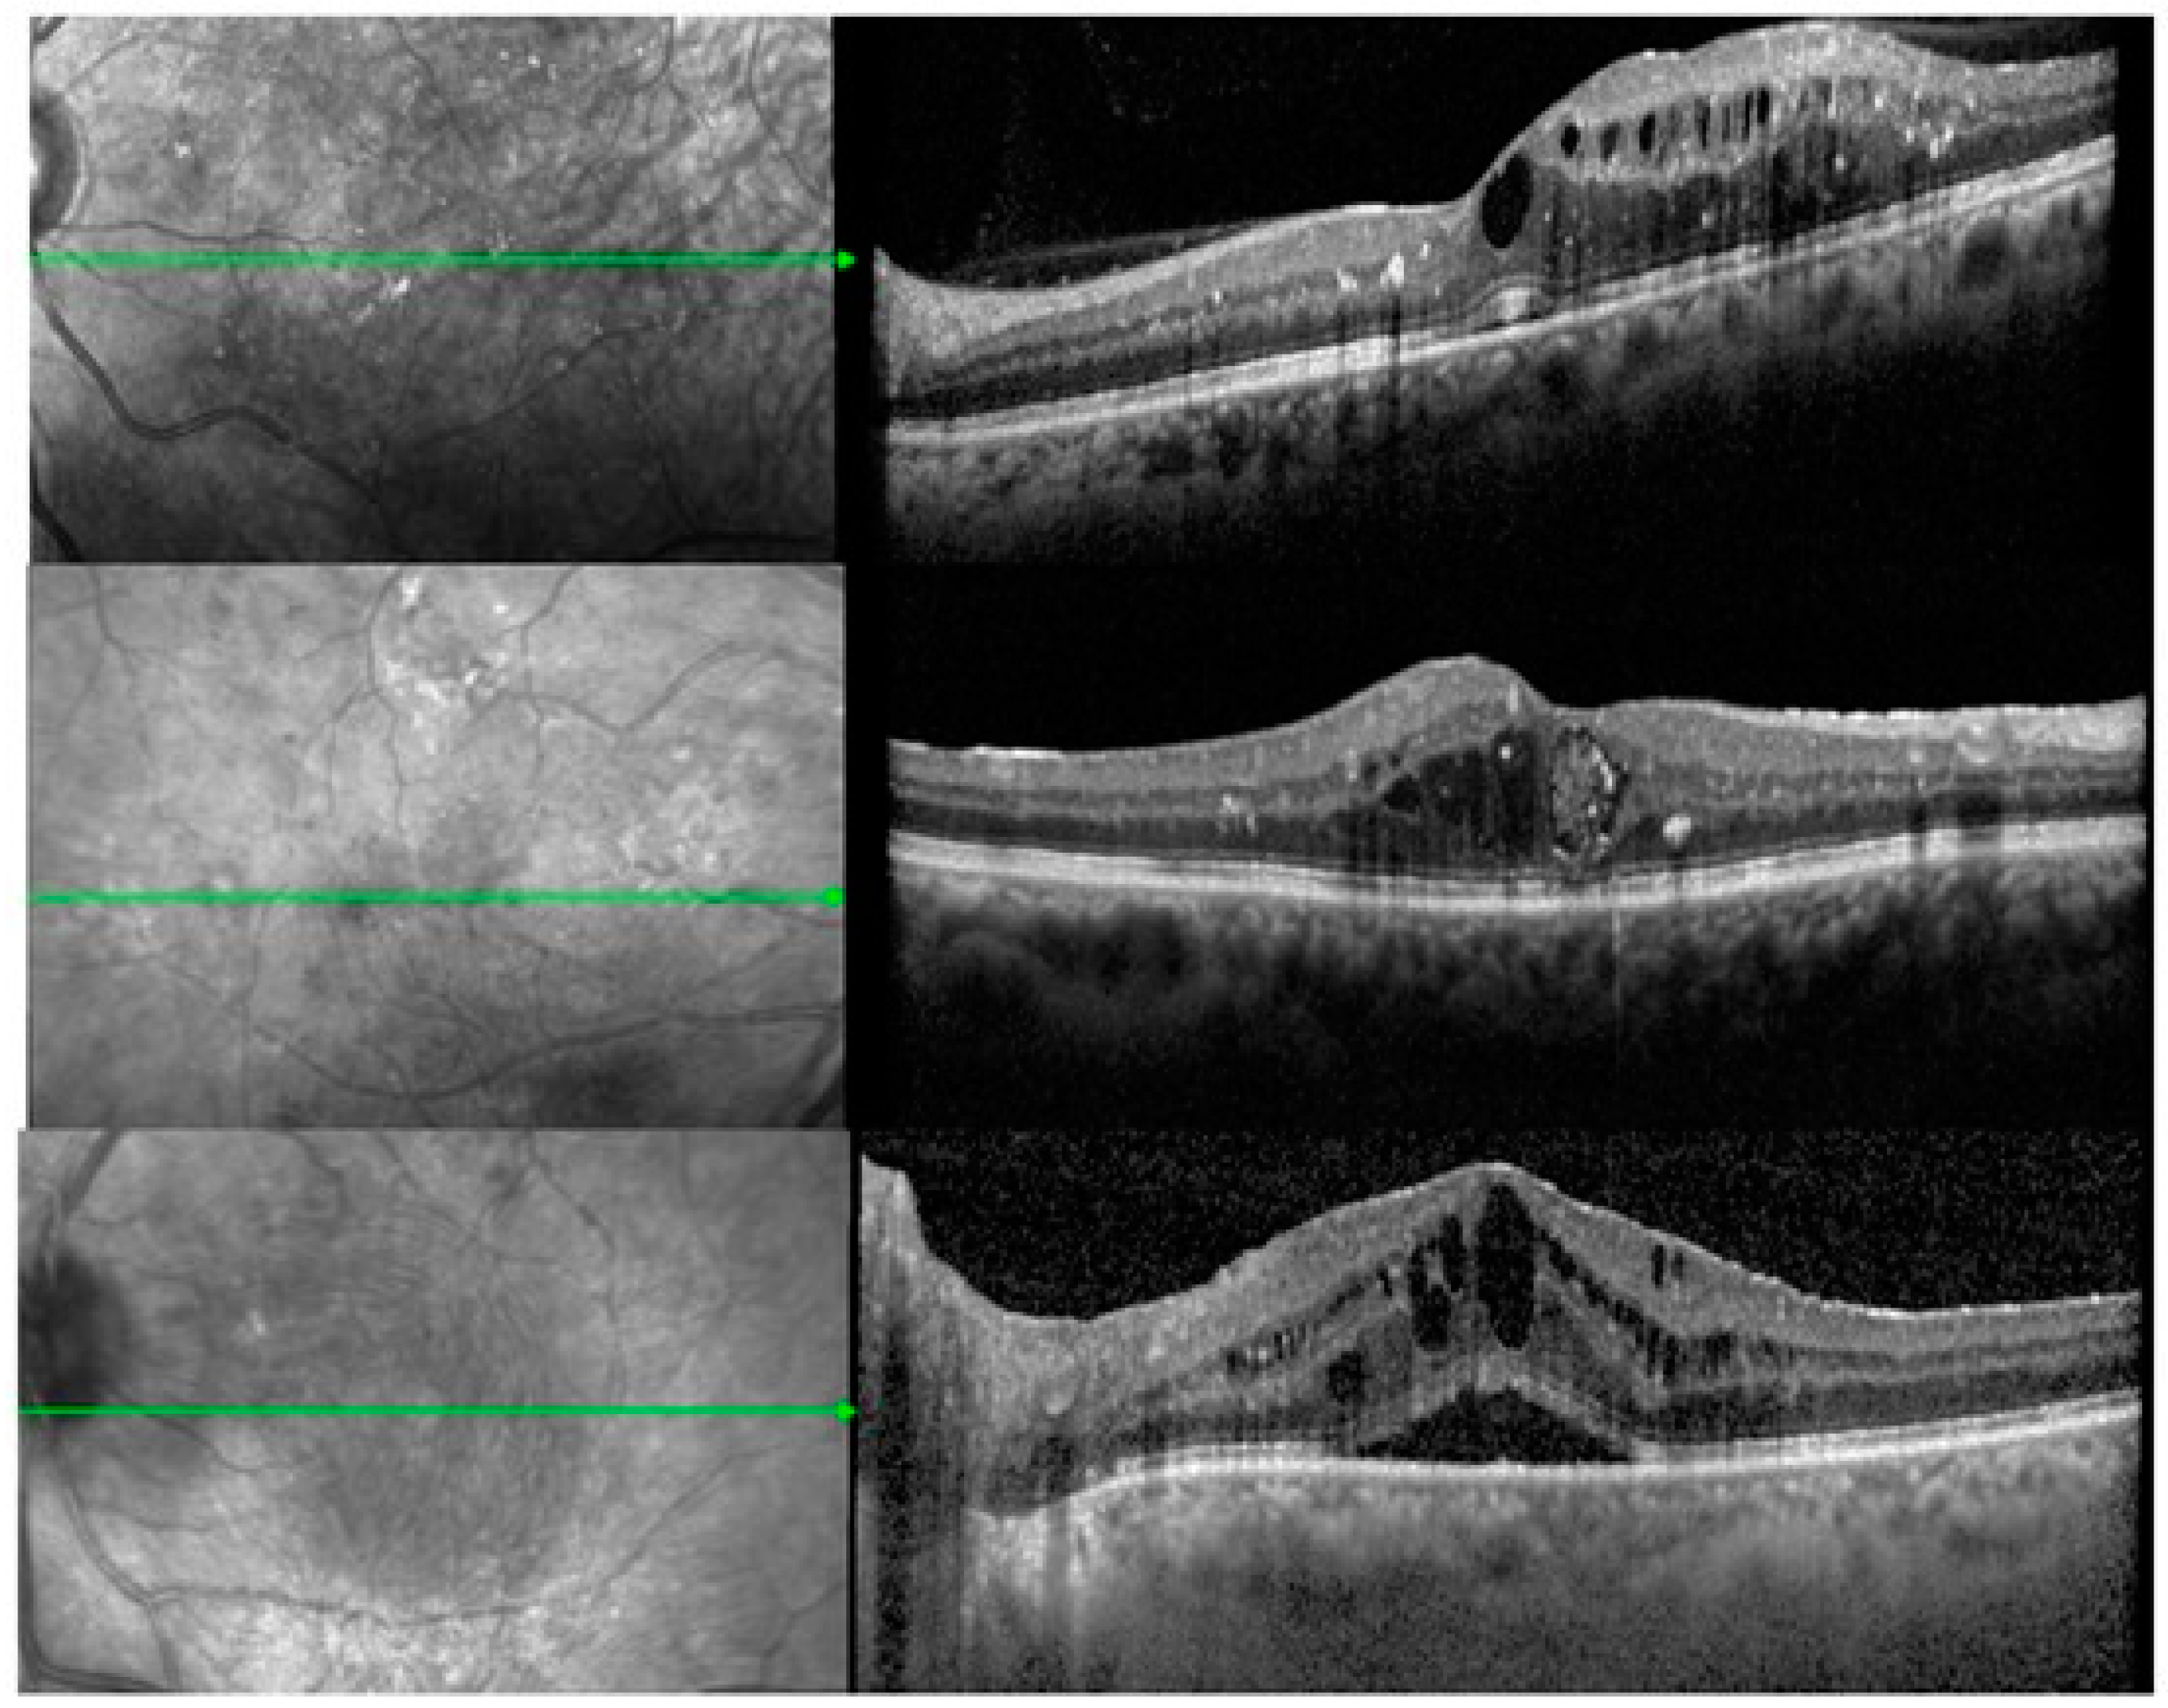

According to the characteristics of DME on SD-OCT images at the baseline visit, the patients were divided into three subgroups: [30] (a) DRT type: a sponge-like retinal swelling of the macula with reduced intraretinal reflectivity; (b) CME type: intraretinal minimally reflective round or oval spaces with highly reflective septa separating cystoid-like cavities that were present in the macular area; and (c) SRD type: the existence of a non-reflective space between the retinal pigment epithelium and the neurosensory retina. As previously described [27], in cases where DRT was combined with CME or SRD, the pattern was appropriately classified as either CME or SRD, and when all subtypes were present (DRT, CME and SRD), the case was classified as SRD. The classification of DME patterns was performed by the same experienced examiner throughout the study. The examiner was masked to the clinical and functional status of the patients while assessing the OCT scans.

Regarding the baseline anatomical characteristics of the DME, as shown on the SD-OCT, 48 (57.1%) had CME-, 15 (17.9%) had DRT- and 21 (25%) had SRD-type. The three morphological types of DME are shown in Figure 1. The mean number of previous anti-VEGF injections in the PT group was 5.1 (SD: 5.7). The total mean CST before the DEX injection was 513.3 μm (SD: 177.8) and the total mean BCVA was 0.8 LogMAR (±0.56) on the EDTRS chart. The IOP before treatment was 14.6 mmHg (SD: 2.7) and no patient was on any antihypertensive topical treatment. The analysis of baseline CST and BCVA between the TN and PT eyes, as well as between the three morphological subgroups, showed no significant differences (TN vs. PT: CST p = 0.32, BCVA p = 0.94) (CME vs. DRT vs. SRD: CST p ≤ 0.001, BCVA: 0.84).

Figure 1. The three morphological types of diabetic macular edema. Diffuse retinal thickening (upper), cystoid macular edema (middle) and serous retinal detachment (lower). The green lines represent scans of the cross sections of the fundus at a specified interval.